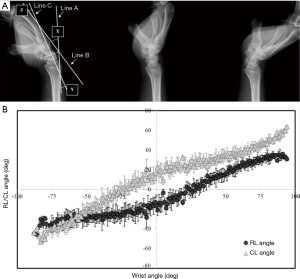

Kawashima et al. developed a sequential X-ray imaging technique and a functional analysis technique to quantitatively assess wrist movement (Figure 4) (16). This study elucidated that changes in the angle between the radiocarpal joint and the midcarpal joint during palmar-dorsiflexion of the wrist have a certain rhythm between these two joints. Their technique can be used not only for quantitative assessments as part of a screening examination but also for pre- and postoperative assessments of recovery. In dynamic imaging, the exposure dose was approximately 0.77 mGy, which is almost 3.5 times the dose for lateral radiography of the wrist joint. Because of advances in FPD technology, the exposure dose has decreased by half (16).

The importance of kinetic analysis of the wrist has been reported in numerous studies, and in recent years, the usefulness of 3D kinetic analysis using CT has been recognized (17,18). However, considering subjects’ exposure to X-rays and the cost, it is difficult to utilize this method as a screening examination in spite of the excellent diagnostic examination. The ideal methodology would be to use sequential X-ray images to first conduct an overview of the kinetics and, if any abnormalities are found, to conduct diagnostic examinations using CT and MRI.